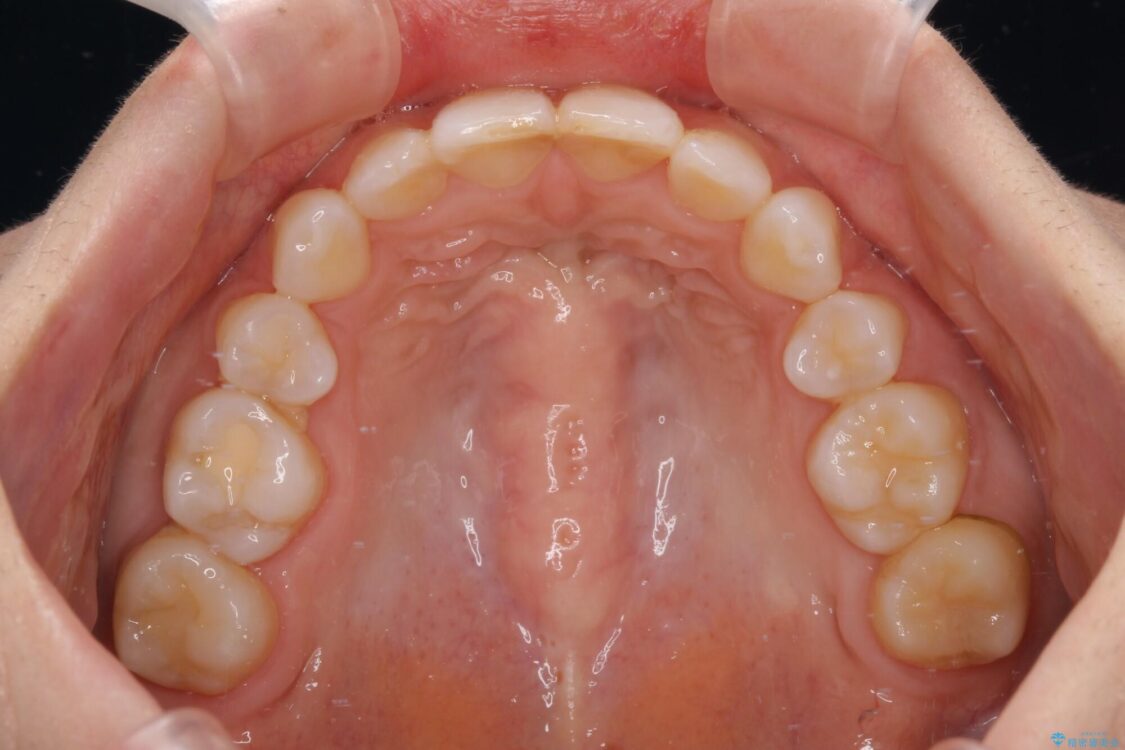

口元の閉じにくさと、奥歯の咬み合わせを気にして来院された患者様です。

左下の大臼歯2本が顕著に舌側に傾斜しているため、まずは奥歯の咬み合わせを改善をし、その後上下左右の第1小臼歯4本を抜歯することで口元を引っ込めながら整えることとしました。

治療前

• 【モニター】出っ歯と咬み合わせを改善 ワイヤー装置の抜歯矯正 治療前画像